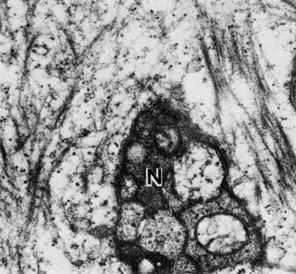

Fig. 25. Nerve axons (N) are visible in the basal cell layer of the epithelium (49,500×). (Courtesy of Drs. Rodrigues, Waring, Hackett, and Donohoo.)